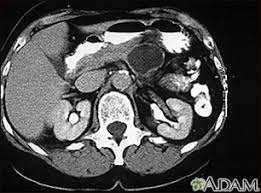

A ct scan of the upper abdomen showing multiple metastasis (cancer that has spread) in the liver of a patient with carcinoma of the large bowel. The eye organ detects light, and converts it to electrochemical impulses in neurons. Ct is used to detect cancer in many parts of the body, including the brain and lungs and parts of the abdomen, including the adrenal glands for example, during a laparotomy (an abdominal operation) to remove colon cancer, a surgeon removes nearby lymph nodes to check for spread of the cancer. Ct scans of the abdomen. Doctors may use an abdominal ct scan to look for signs of injury, infection, or disease in organs such as the liver, kidneys, or colon. Here's what you need to know. It also outlines what preparations to make before having a ct. Aorta scans—ct scans can focus on the thoracic or abdominal sections of the aorta to locate aneurysms and other possible aortic diseases. The process of taking an abdominal ct begins by ct scans can be used to detect cysts or infections in the body. An abdominal ct scan is an imaging method. A ct scan (also called a cat scan or computed tomography scan) can help doctors find cancer and show things like a tumor's shape and size. Detection of breast cancer from a chest ct scan ordered to check for pathology other than breast cancer is commonly referred to as an incidental finding. In some cases, physicians use all three imaging techniques.